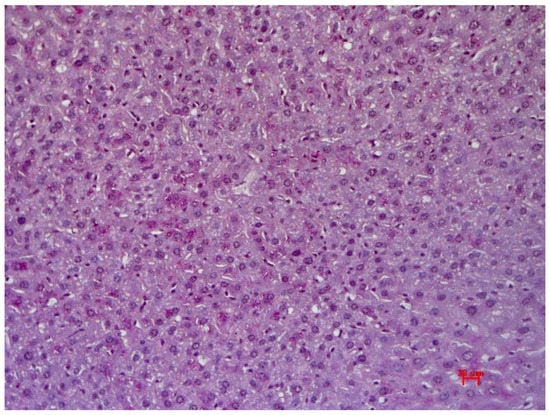

3.3. Histological Examination